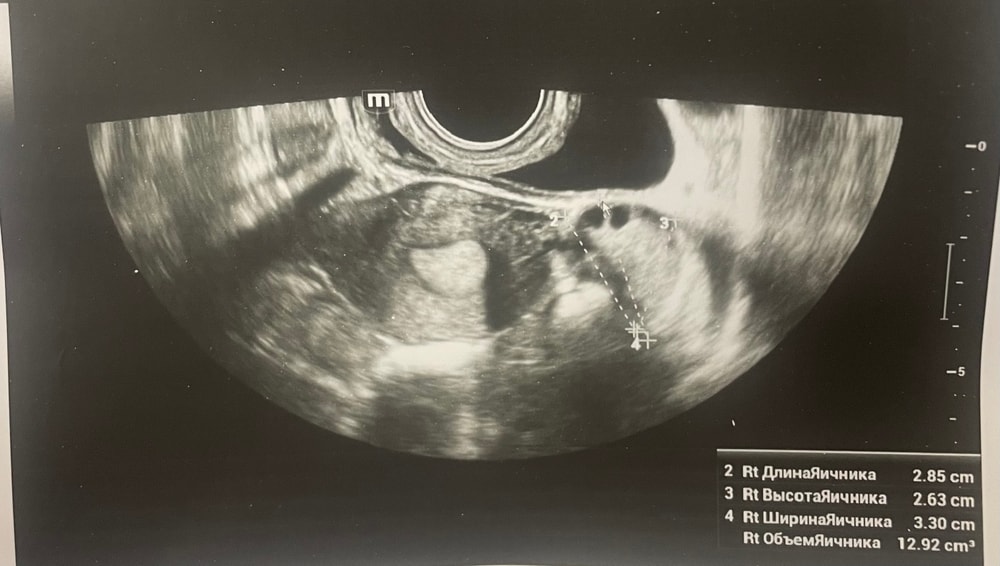

Прошу советаДобрый день, мы с мужем планируем беременность и в этом месяце произошло что то странное… дата начала последней менструации 4 октября закончилась 8, овуляцию отслеживала всю неделю почти сначала были бледные еле заметные полоски, 23 октября жирные четкие полоски, 24 октября стала чуть бледнее но яркая, вообщем положительный ещё был, с 25 числа тест уже отрицательный, через день после овуляции 26 числа стала странно себя чувствовать и во время овуляции болел живот то справа то с лева и поясница, так через день после начали болеть соски грудь вообще не болела, живот то болит то нет и с поясницей также, позже появилась небольшая изжога, нога немеет правая не знаю с чем связано), все это началось за 2 недели до месячных в середине цикла скажем так 29 числа пошла на узи спустя 6 дней грубо говоря гиня сказала что у меня была очень хорошая овуляция, что её признаки сохраняются до сих пор так скажем, желтое тело СПРАВО 20 мм, мои симптомы и все это очень похоже на беременность сказали большая вероятность, я очень была рада и надеялась, после узи появились выделения с комочками, до этого были просто густые белые выделения, утром тоже самое, пошла опять к гинекологу она сказала это может быть при ранец беременности сказала какие свечи купить, вечером я попала в не большое ДТП, удар был в поясницу и копчик, живот начал тянуть и поясница сильно болеть, начала болеть сама грудь помимо сосков, живот прошел относительно быстро, а вот поясница ломит до сих пор, решила сходить ещё раз на узи очень испугалась, на узи я пошла 31 через два дня после предыдущего и уже к другому гинекологу, моя на больничном, она сказала, что у меня отсутствуют даже косвенные признаки беременности и желтое тело с ЛЕВО А НЕ С ПРАВО, я не понимаю как такое может быть, очень расстроилась и совсем забыла про фото узи, она мне его не дала только заключение и как выяснилось уже не дадут оно не сохранилось, сказали переделывать, я очень доверяю своему гинекологу, но по заключению второго врача о беременности не может быть и речи в этом цикле, я не понимаю как желтое тело оказалось с лево если оно точно было справа в этом я уверена, а вторая врач уверяет во Братном, живот в обуляцию хоть и болел с двух сторон но больше справа помойму, вообщем я не понимаю есть ли шанс что я беременна или все таки нет, я понимаю что это слишком рано, до задержки ещё 4 дня, но мне плохо уже неделю по симптомам даже больше это же не просто так, я прикреплю фото заключения, могу ли я быть беременна, если посмотреть на эти заключения хотябы, подскажите пожалуйста фото узи относятся к 29.10, без фото 31.10